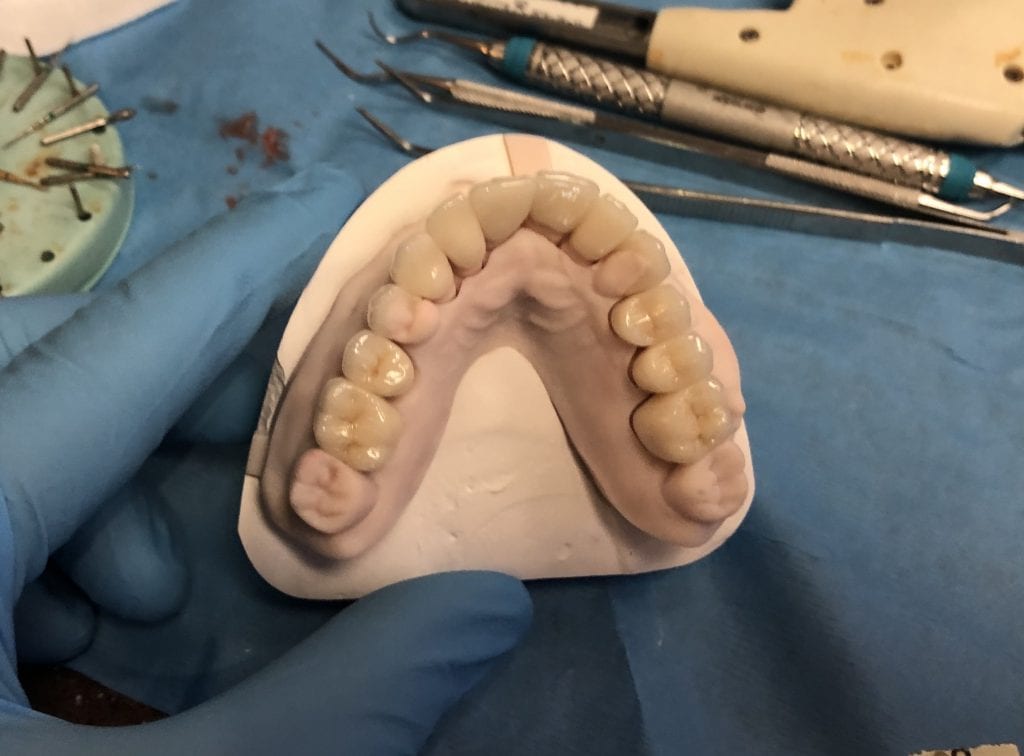

Anterior preps scanned along with the opposing and the initial bite

segmental imaging to building a master model

upper and lower models related to each other for design